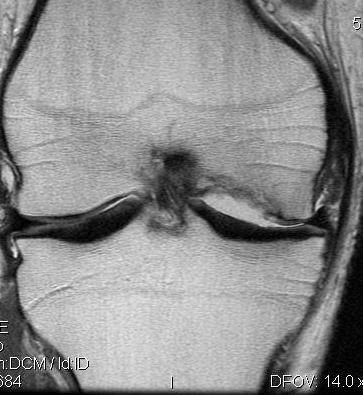

MRI

May be normal in early stages

TI

- low signal areas in subchondral region

T2

- low signal

- surrounding high intensity signal secondary to oedema